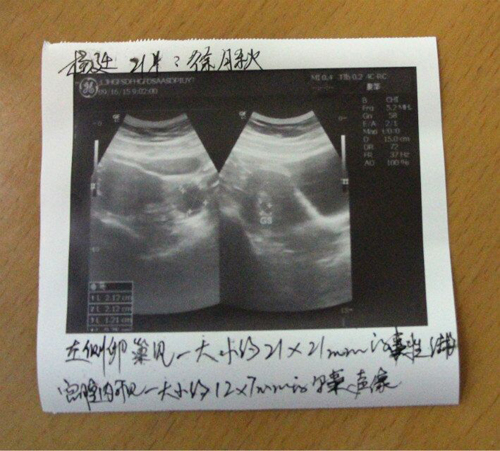

(杨廷的B超影像)

杨廷说,之前在别的医院治疗,医生都是只给她开西药,吃了不仅没效果,反而身子越来越差,但是玛丽医院不一样,徐主任根据她的具体情况,运用中药加西药的结合调养,让她一个月就成功怀孕了。出于对医院的信任,在治疗过程中,她非常积极主动配合医生,这也是她顺利怀上孩子最关键的因素。现在,她不孕六年的表姐听说她成功怀孕了,也准备过来医院接受治疗,祝愿她们都能成功拥有自己的宝宝。